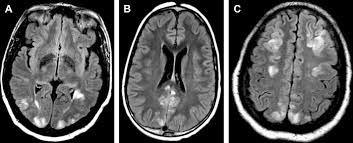

Frontiers Posterior Reversible Encephalopathy Syndrome And Reversible Cerebral Vasoconstriction Syndrome Clinical And Radiological Considerations Neurology